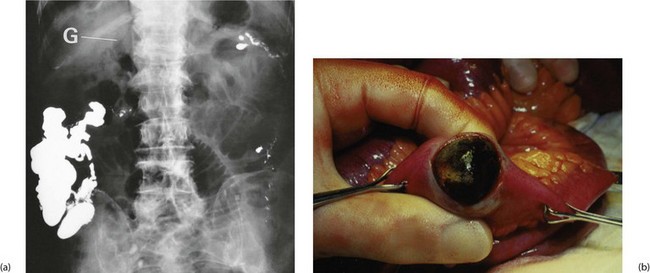

These uncommon complications of gallstones occur when the inflamed gall bladder becomes adherent to the adjacent duodenum and a stone ulcerates through the wall to form a cholecysto-duodenal fistula. The fistula decompresses the obstructed gall bladder and allows stones to pass into the bowel and gas to enter the biliary tree. The condition is usually painless and unsuspected but may be diagnosed on plain abdominal X-ray by the presence of gas outlining the biliary tree (see Fig. 20.7). Sometimes a fistula is discovered at operation.

Occasionally, a solitary cholesterol stone passing into the bowel is so large that after traversing the small bowel it impacts in the narrowest part, the distal ileum, causing small bowel obstruction or gallstone ileus (see Fig. 20.7). This occurs in the elderly and presents as an unexplained intermittent and sometimes incomplete small bowel obstruction. Unfortunately, the diagnosis is often difficult to make as the stone is usually radiolucent so in an elderly patient with distal small bowel obstruction, the diagnosis needs to be considered and can be confidently made if gas is recognised in the biliary tree on a plain abdominal X-ray.

Fig. 20.2 X-ray of radiopaque gallstone

Plain abdominal X-ray showing large radiopaque gallstone in the right upper quadrant. Note that the stone is obviously laminated, having built up in layers over many years. Note also that only 10% of mixed stones are radiopaque